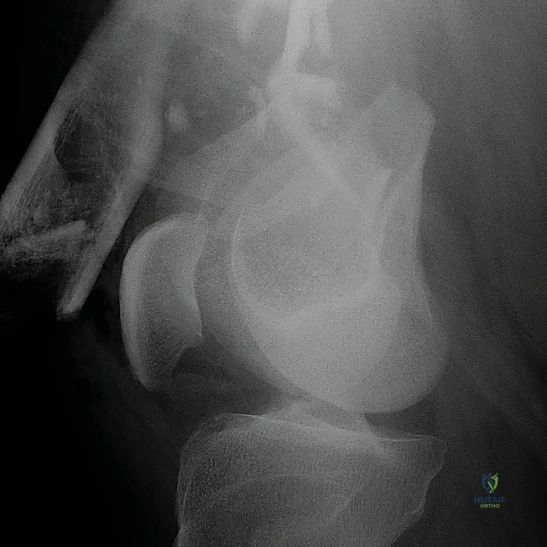

التشخيص الدقيق: حجر الأساس للعلاج الناجح

في عيادة الأستاذ الدكتور محمد هطيف في صنعاء، لا يتم ترك أي مجال للصدفة. يتم إجراء تقييم شامل يبدأ بـ:

- التقييم السريري المبدئي: فحص النبض والأعصاب للتأكد من عدم وجود إصابات وعائية أو عصبية مصاحبة.

- الأشعة السينية (X-Rays): أخذ صور من زوايا متعددة (أمامي خلفي، وجانبي) لتحديد موقع الكسر ونوعه.

- الأشعة المقطعية (CT Scan): وهي ضرورية جداً في كسور عظم الفخذ البعيدة، خاصة إذا كان الكسر يمتد إلى داخل مفصل الركبة (Intra-articular fractures). تساعد الأشعة المقطعية الدكتور هطيف على بناء نموذج ثلاثي الأبعاد للكسر، مما يسهل التخطيط الجراحي وتحديد أماكن وضع المسامير بدقة.